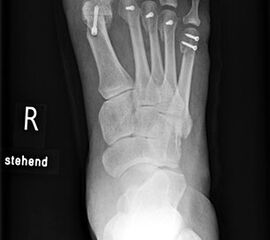

Die Fäden werden nach der 2. postoperativen Woche gezogen. Der Verbandsschuh wird für 4-6 Wochen getragen, anschließend erfolgt eine Röntgenkontrolle (Abb.16). Das Führen eines Kraftfahrzeuges mit diesem Schuh ist nicht gestattet. Eine Ausnahmekombination stellt die Operation des linken Fußes und Automatik-Fahrzeug dar.

Aus der klinischen Erfahrung heraus können die Patienten, bei unauffälligem Röntgenbild weiter mit einer entsprechenden Einlagenversorgung mit retrocapitaler Abstützung und ggf. notwendigen Modifikationen im weiten, bequemen Konfektionsschuh mobilisiert werden. Die klinischen Verlaufskontrollen in den letzten 14 Jahren haben gezeigt, dass bei korrekter Stellung zu diesem Zeitpunkt die osteotomierten Köpfchen auch in dieser Position verbleiben. Sollte eine korrekturbedürftige Fehlstellung vorliegen, ist diese 4 Wochen nach Primär-OP mit einem geringeren operativen Aufwand durchzuführen.